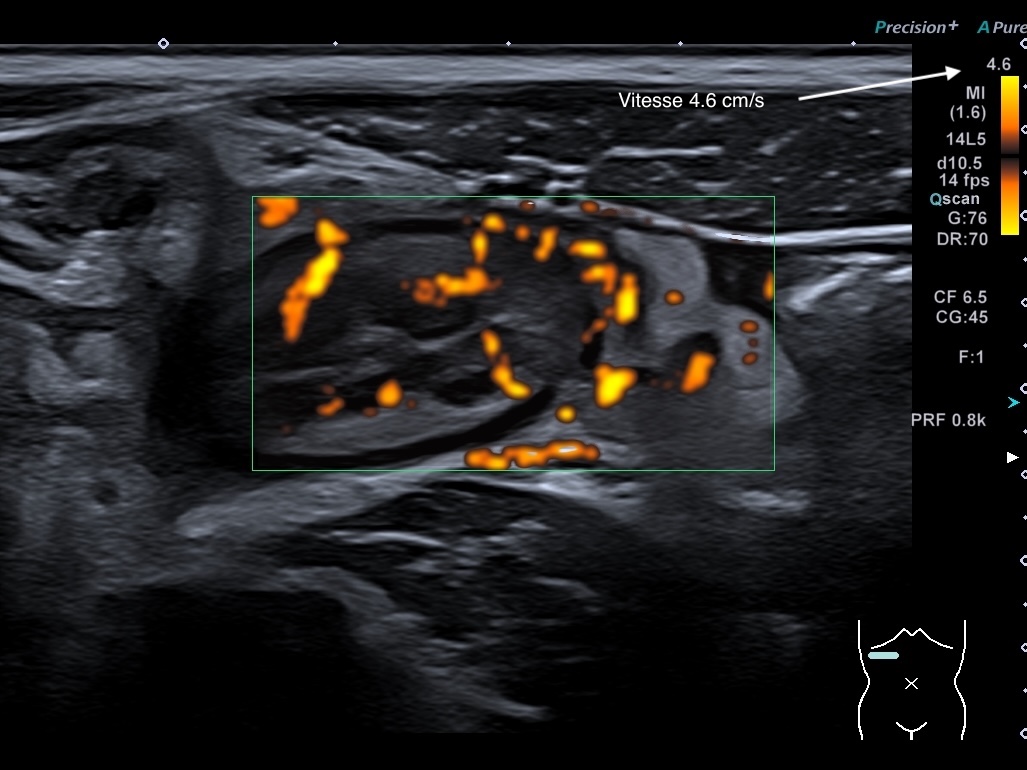

Doppler énergie LImberg 3 (activité intense de la paroi+ graisse) même patient, pas d'indication de sens du flux

Doppler microcirculation LImberg 3 (activité intense de la paroi+ graisse)

même patient, pas d'indication de sens du flux